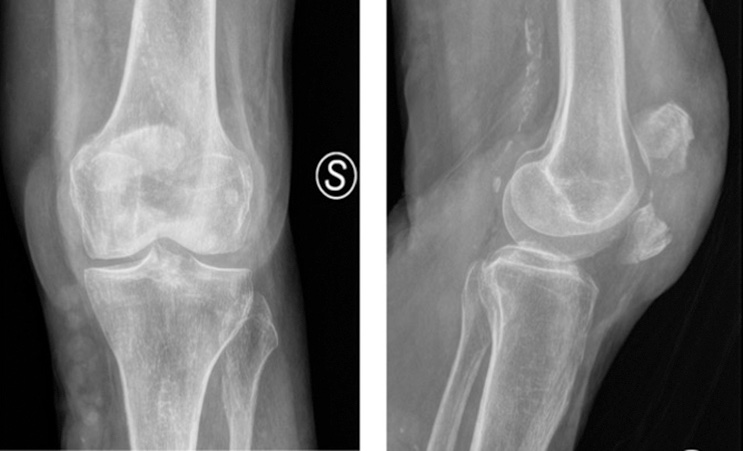

Le fratture della rotula, nonostante un’osteosintesi adeguata, possono causare danno alla superficie articolare cartilaginea con lo sviluppo nel corso del tempo di un’artrosi secondaria; in questo caso una soluzione per il trattamento del dolore cronico è la protesizzazione totale del ginocchio o della sola femoro-rotulea, nel caso gli altri compartimenti risultassero indenni. Oltre a questo dato, a seguito di una frattura rotulea, possono verificarsi ipotrofia e ipostenia della muscolatura con conseguente limitazione nel movimento.